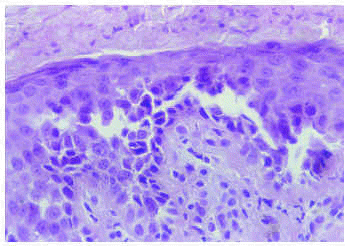

El hemograma y la bioquímica de rutina fueron normales. Se practicó una biopsia de una de las lesiones del cuello (figs. 3 y 4).

Fig. 4.--Detalle histológico a mayor aumento.

Histopatológicamente, en la epidermis se observaban hendiduras suprabasales que contenían queratinocitos acantolíticos. Algunas de las células mostraban disqueratosis, pero no se apreciaban cuerpos redondos. La superficie de la epidermis se mostraba hiperqueratósica, con orto y paraqueratosis. En la dermis existía un moderado infiltrado inflamatorio perivascular compuesto por linfocitos e histiocitos.

El estudio histopatológico se caracteriza por la existencia de acantolisis, edema intercelular, aspecto de «pared en ladrillos desmoronada» de la epidermis y en ocasiones presencia de células disqueratósicas, hecho que plantea el diagnóstico diferencial con la enfermedad de Darier. El estudio con inmunofluorescencia directa e indirecta es negativo, a diferencia de las enfermedades ampollosas autoinmunes. Con el microscopio electrónico se observa un defecto en la adhesión desmosómica, con separación de los tonofilamentos9.